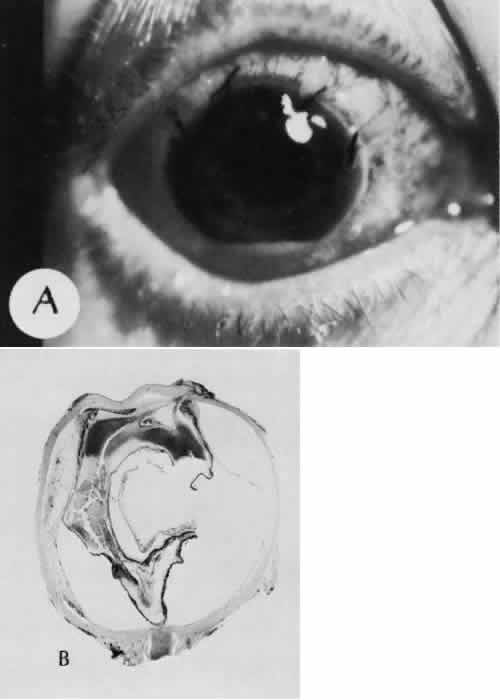

Many complications originate from so-called surgical confusion (Fig. 24). Most arise from a lack of knowledge, a lack of judgment, or problems in perception. At times, lack of attention to detail in preoperative planning may lead to a drug reaction, inadequate anesthesia, misplacement of incisions and sutures, or a patient who is unable to control a cough reflex. What is recognized histologically as the immediate cause of the problem may well have its origin in improper planning of the procedure.

Fig. 24. An unusual complication of cataract surgery. A. An unsuspected uveal mass was noted in the region of the pupil following cataract extraction. The mass was determined to be a metastatic carcinoma. The globe was enucleated. B. In a section of the enucleated globe, extensive tumor (T) can be identified though one hemisphere of the choroid, causing a secondary retinal detachment (RD). The detached retina is herniated through the cataract wound. (Hematoxylin-eosin stain; × 5.)